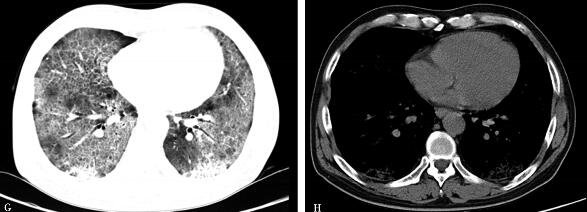

治疗半年后,患者气短好转,血气分析正常,2011年9月1日复查胸部CT(图

3)示:双肺纹理清晰,双肺磨玻璃影全部吸收。2014年2月电话随访,患者正常生活和工作,无不适主诉,未再复查胸部CT和血CEA等。

图3